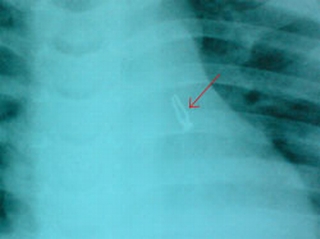

Kết quả là tình trạng phổi bị viêm ở cả 2 bên, bên phổi trái còn bị xẹp một phần. Chụp phim kiểm tra lại giúp xác định được có hình ảnh vật kim khí trong lồng ngực bên trái.

Nội soi đường thở thì thấy có nhiều mủ đục ở cuống phổi bên trái. Ở giữa ổ mủ gắp ra được một bóng đèn điện nhỏ, lọai đèn trang trí làm đẹp nhà cửa.